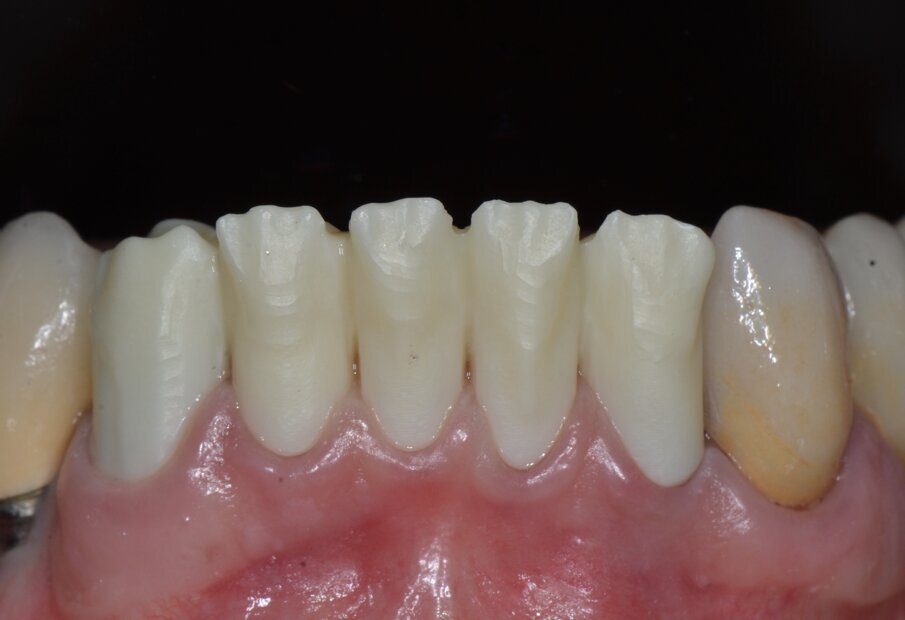

Da un punto di vista protesico verranno eseguite corone singole in zirconia stratificata sugli elementi 13-12-11-21-22 e una faccetta in disilicato di litio sul 23. A causa della notevole rotazione dei due incisivi centrali in fase di ceratura abbiamo optato per due corone complete anziché due faccette per una migliore distribuzione degli spazi protesici dei quattro incisivi (Fig. 8). Il gruppo frontale inferiore invece verrà protesizzato con corone in zirconia stratificata sugli elementi 32-31-41-42-43 splintate per compensare una mobilità di grado 1 dei quattro incisivi.